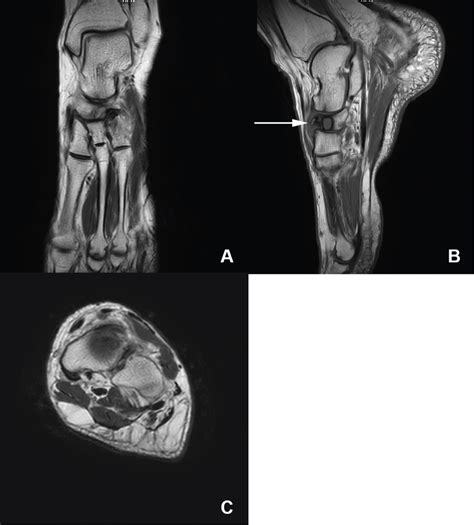

Diagnosing Mueller Weiss Syndrome requires a comprehensive evaluation by a foot and ankle specialist. Because the symptoms can mimic other conditions like tarsal coalition or arthritis, imaging is essential for a precise diagnosis.

MRI Highly sensitive; used to detect early signs of edema and bone marrow changes.

CT Scan Best for detailed assessment of bone morphology and planning potential surgical intervention.